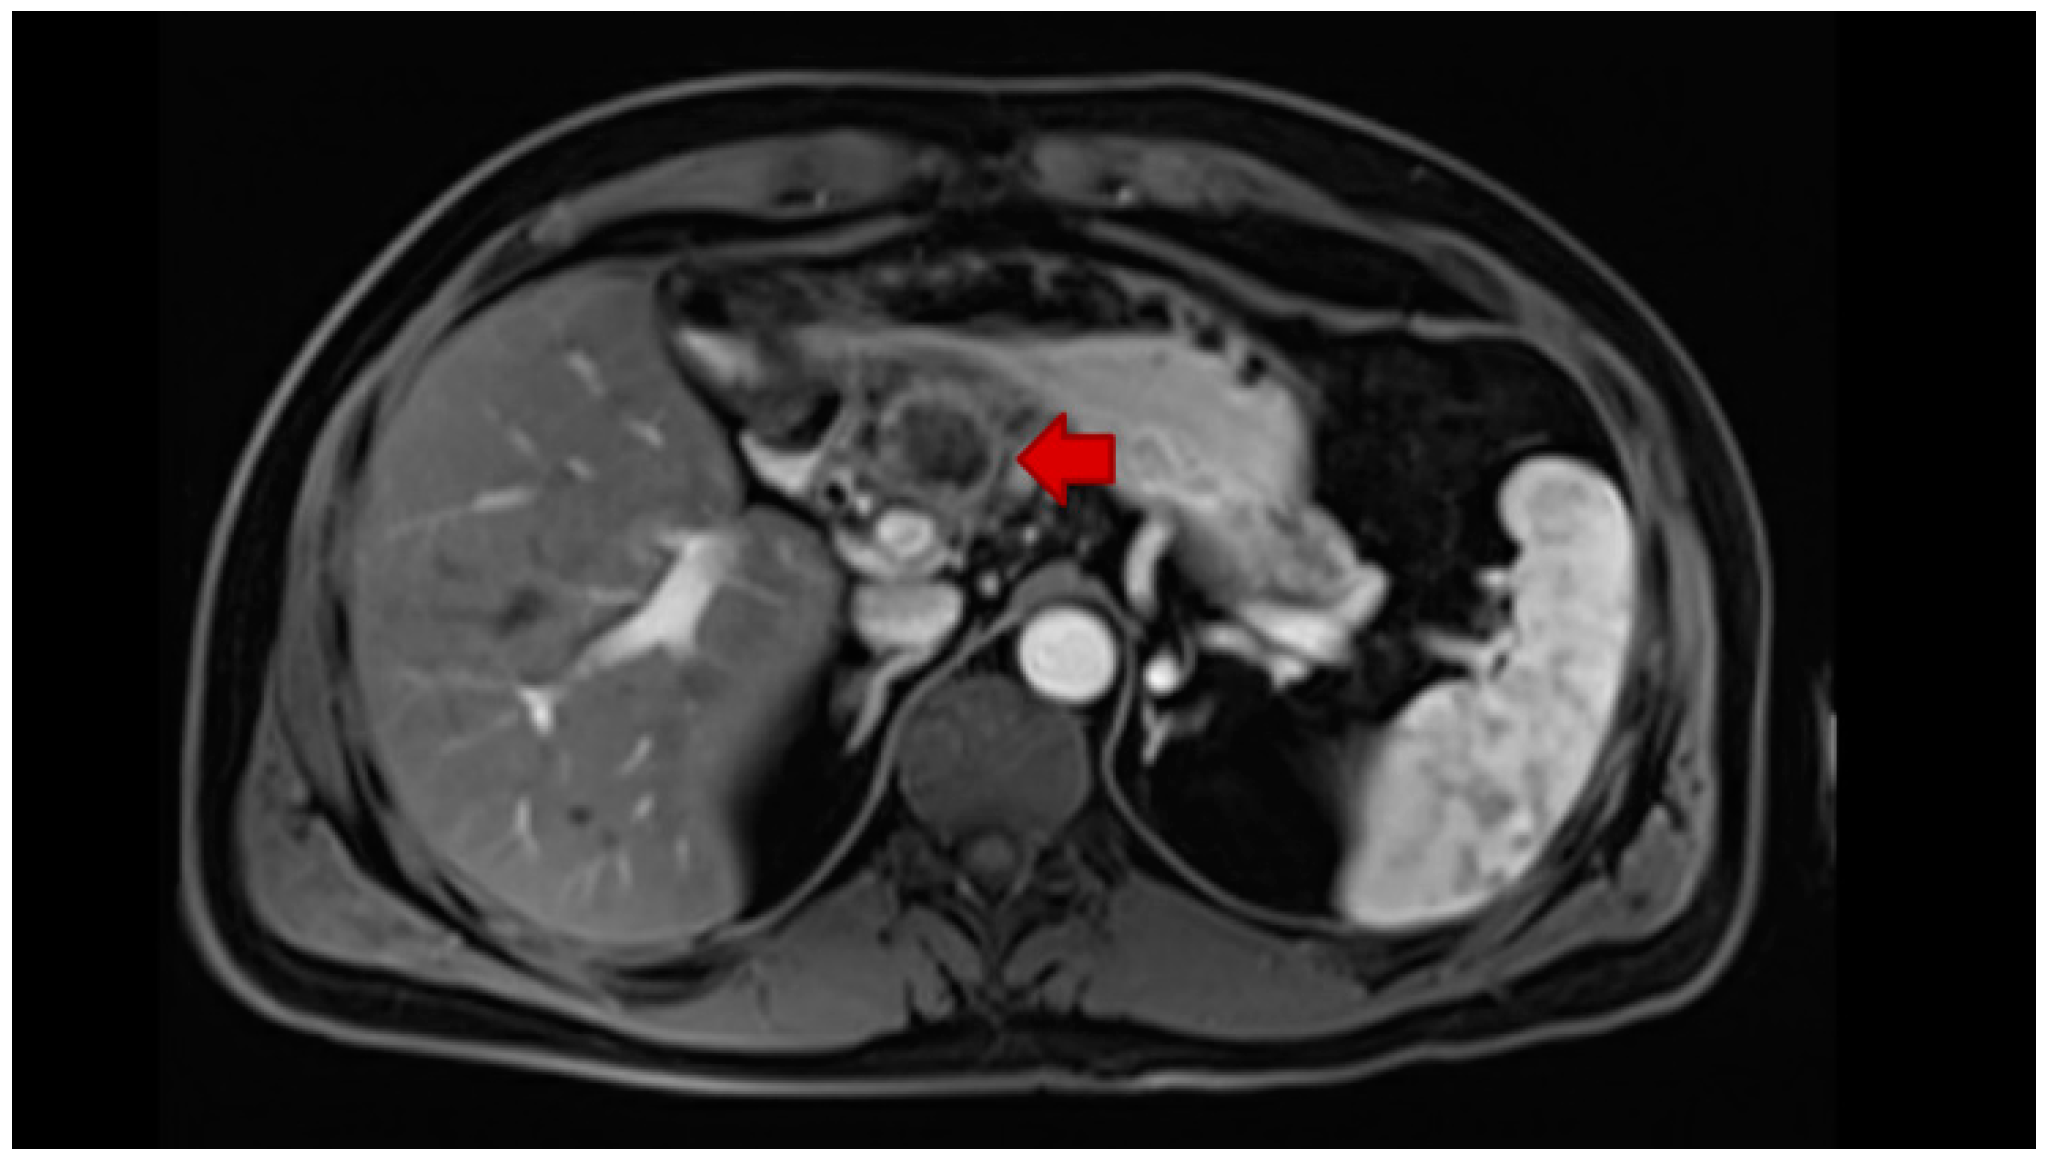

- Fábrega-Foster, K.; Ghasabeh, M.A.; Pawlik, T.M.; Kamel, I.R. Multimodality imaging of intrahepatic cholangiocarcinoma. HepatoBiliary Surg. Nutr. 2017, 6, 67–78. [Google Scholar] [CrossRef] [PubMed]

- Seo, N.; Kim, D.Y.; Choi, J.Y. Cross-sectional imaging of intrahepatic cholangiocarcinoma: Development, growth, spread, and prognosis. Am. J. Roentgenol. 2017, 209, W64–W75. [Google Scholar] [CrossRef]

- Yang, C.M.; Shu, J. Cholangiocarcinoma Evaluation via Imaging and Artificial Intelligence. Oncology 2020, 98, 1–12. [Google Scholar] [CrossRef]

- Kim, R.; Lee, J.M.; Shin, C.I.; Lee, E.S.; Yoon, J.H.; Joo, I.; Kim, S.H.; Hwang, I.; Han, J.K.; Choi, B.I. Differentiation of intrahepatic mass-forming cholangiocarcinoma from hepatocellular carcinoma on gadoxetic acid-enhanced liver MR imaging. Eur. Radiol. 2016, 26, 1808–1817. [Google Scholar] [CrossRef]